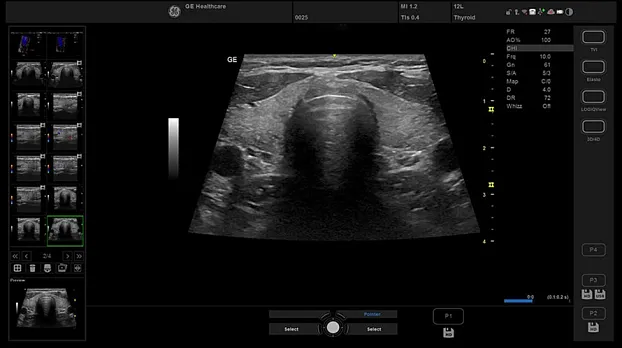

Клинические изображения

- Поверхностные органы

- L5-11-RS Линейный датчик, широкополосный, мультичастотный с диапазоном частот 3,7-13,0 МГц

- L6-12-RS Линейный датчик, широкополосный, мультичастотный с диапазоном частот 4,0-13,0 МГц